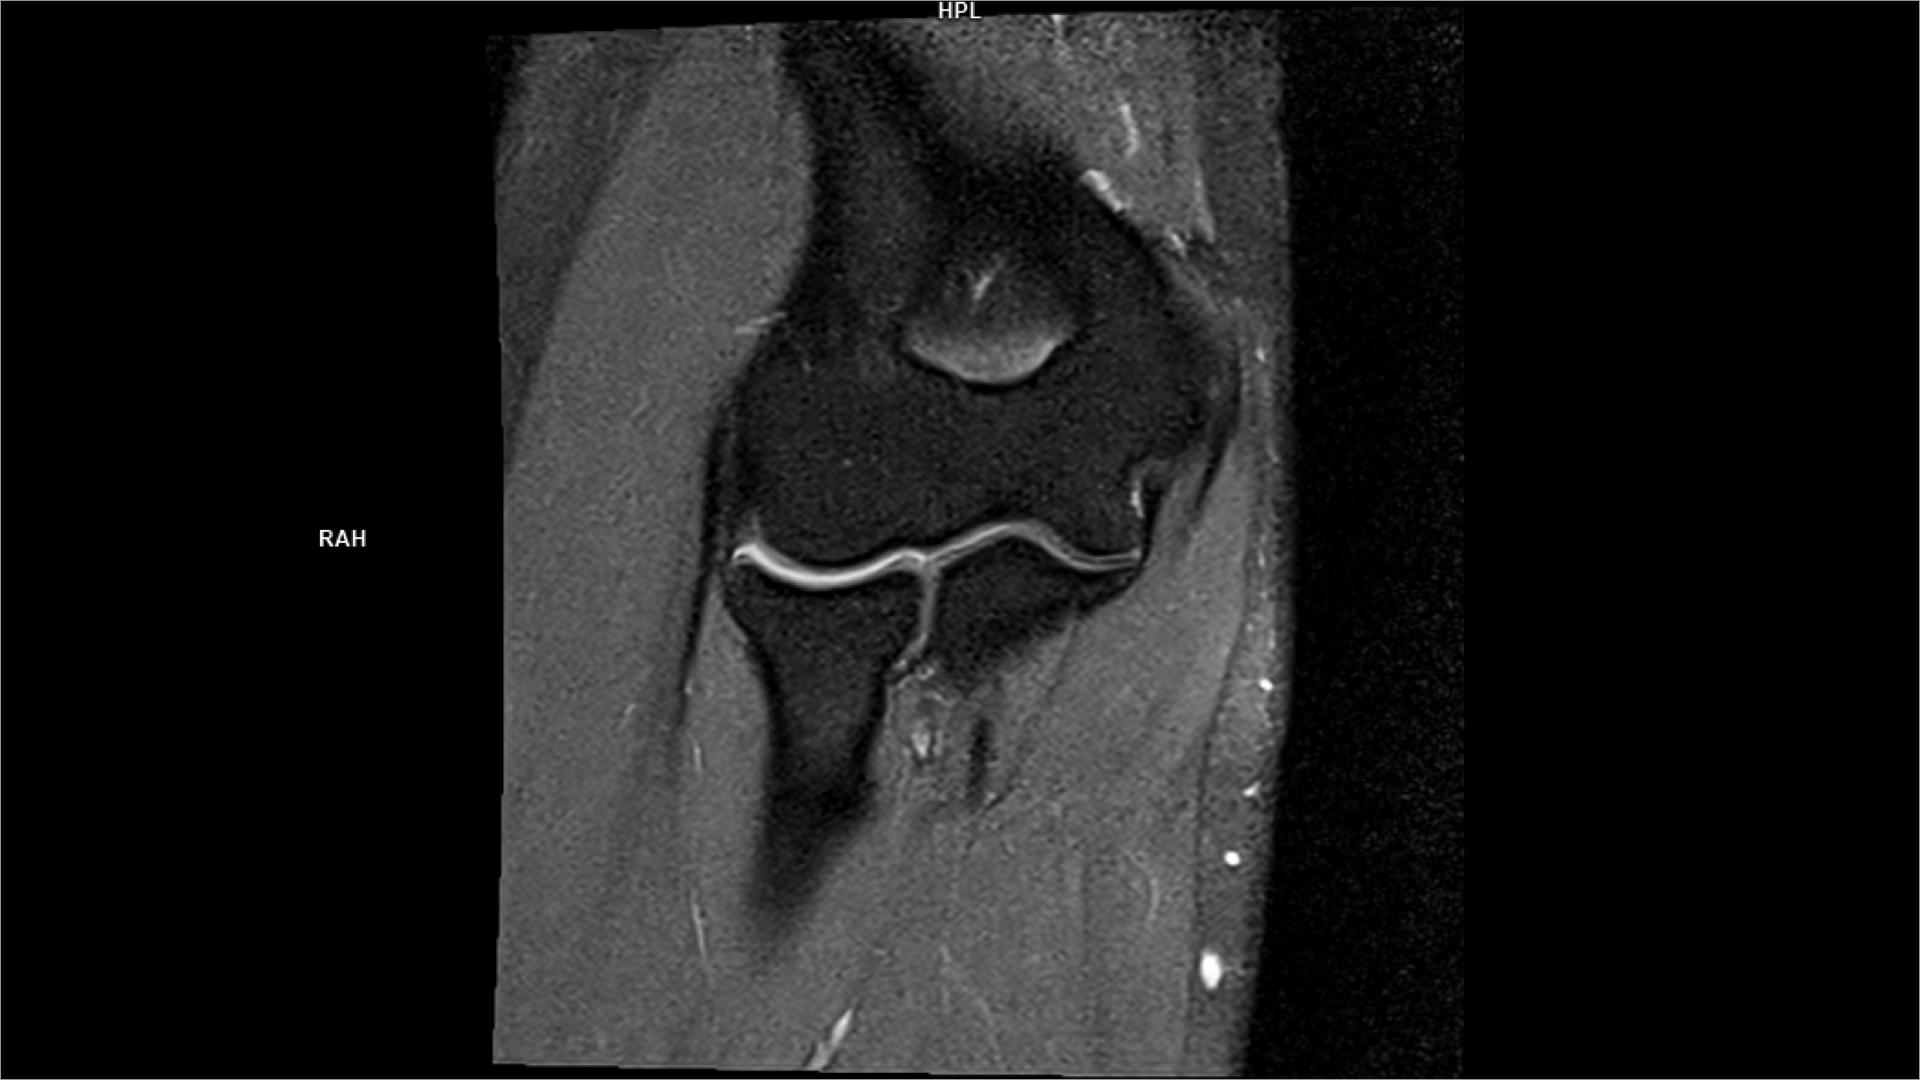

Coronal T2 weighted MRI image of a knee with a chronicA Openi Coronal Pd Mri The mri allows accurate assessment of any pathologic changes of the structures of the shoulder, including the glenoid labrum, the humeral head, the articular. Rotator cuff tears are the most common cause of shoulder pain and result in loss of strength and loss of stability of the shoulder. Protocol specifics will vary depending on mri hardware and software, radiologist and. Coronal Pd Mri.

Coronal MRI of the right knee revealing intraarticular Openi Coronal Pd Mri In this article we will discuss: The role of mri in. Rotator cuff tears are the most common cause of shoulder pain and result in loss of strength and loss of stability of the shoulder. Protocol specifics will vary depending on mri hardware and software, radiologist and referrer preference, patient. Many standard shoulder protocols will include the following fast spin. Coronal Pd Mri.